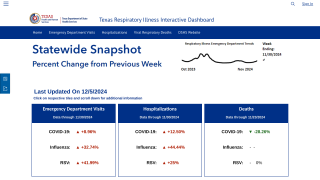

Separately, the CDC reported the key influenza indicators for the week ending February 16, 2019, are as follows:

- The proportion of outpatient visits for influenza-like illness (ILI) increased to 5.1%, which is above the national baseline of 2.2%. All 10 regions reported ILI at or above their region-specific baseline level.

- New York City and 30 states experienced high ILI activity; the District of Columbia and 11 states experienced moderate ILI activity; six states experienced low ILI activity; the U.S. Virgin Islands and three states experienced minimal ILI activity, and Puerto Rico had insufficient data.

- The geographic spread of influenza in Puerto Rico and 48 states was reported as widespread; one state reported regional activity; the District of Columbia reported local activity; the U.S. Virgin Islands and one state reported sporadic activity, and Guam did not report.

- A cumulative rate of 27.4 laboratory-confirmed influenza-associated hospitalizations per 100,000 population was reported. The highest hospitalization rate is among adults 65 years and older (75.6 hospitalizations per 100,000 population).

- The proportion of deaths attributed to pneumonia and influenza (P&I) was below the system-specific epidemic threshold in the National Center for Health Statistics (NCHS) Mortality Surveillance System.